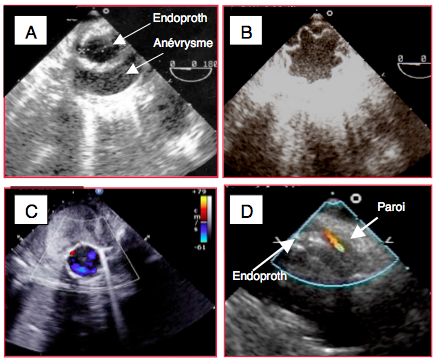

- Endoprothèse aortique : contrôle du passage du guide dans la vraie lumière en cas de dissection aortique ; contrôle de la position de l’endoprothèse par rapport à un anévrysme, une déchirure intimale, ou la sous-clavière gauche (Figure 25.239).

Figure 25.239 : Endoprothèse de l'aorte thoracique descendante. A: vue court-axe dun anévrysme de l'aorte descendante avec une endoprothèse en place. B: endoprothèse mal expandue; au vu de cette image, il faut ré-expandre l’endoprothèse au moyen d’un ballon. C: flux normal dans une endoptothèse située à l'intérieur d'un gros anévrysme thrombosé. D: fuite entre la prothèse et la paroi.